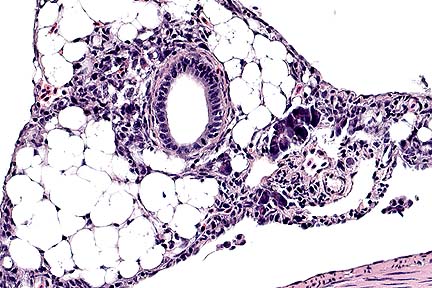

Ulceration and moderate subacute submucosal inflammation in the trachea of a dog with toxic epidermal necrolysis. (HE, 200X, 63K)

Loss of tracheal mucosal epithelium and a submucosal infiltrate of macrophages, lymphocytes, plasma cells and rare neutrophils in a dog with toxic epidermal necrolysis. (HE, 400X, 60K)

Contributor's Diagnosis and Comments: Severe necrotizing tracheitis associated with toxic epidermal necrolysis.

Toxic epidermal necrolysis (TEN) is a life-threatening, ulcerative skin disease that occurs rarely in the dog and cat. The facial skin, mucocutaneous junctions and oral mucosa are commonly involved. Necrosis of the mucosa of the trachea, large bronchi, pharynx and esophagus can also occur (Gross et al, 1992). Drug hypersensitivity reactions, neoplasia and concurrent infections have been implicated in the pathogenesis, although many cases are idiopathic. In TEN, early full-thickness epidermal necrosis occurs with minimal inflammatory reaction. Leukocyte infiltration occurs following ulceration. In this case, the ulcerative skin disease was advanced, with marked secondary pyoderma in areas of ulceration. This dog had no known exposure to drugs commonly associated with TEN, nor was there evidence of underlying infectious disease on postmortem examination.

AFIP Diagnosis: Trachea: Tracheitis, ulcerative, subacute, focally-extensive, severe, with pseudomembrane and squamous metaplasia, Pomeranian, canine.

Conference Note: Toxic epidermal necrolysis has been associated with drug therapy, systemic neoplasia, host vs. graft reactions, and bacterial infection. The pathogenesis is unknown. It is believed that cell-mediated immune mechanisms destroy the epidermal basal cells. Direct immunofluorescence in two cases of drug-induced TEN revealed intercellular fixation of immunoglobulins and complement in the basal cell layer of the epidermis.

Histologically, TEN is characterized by coagulative necrosis of the epidermis with minimal dermal inflammatory infiltrates. The necrotic epidermis separates from the dermis to form variably sized vesicles, which rupture, forming ulcers. Ulceration often induces a secondary dermatitis with predominance of neutrophils. Ultrastructural studies show condensation of tonofilaments around pyknotic nuclei and the disapperance of all organelles within the affected epithelial cells.